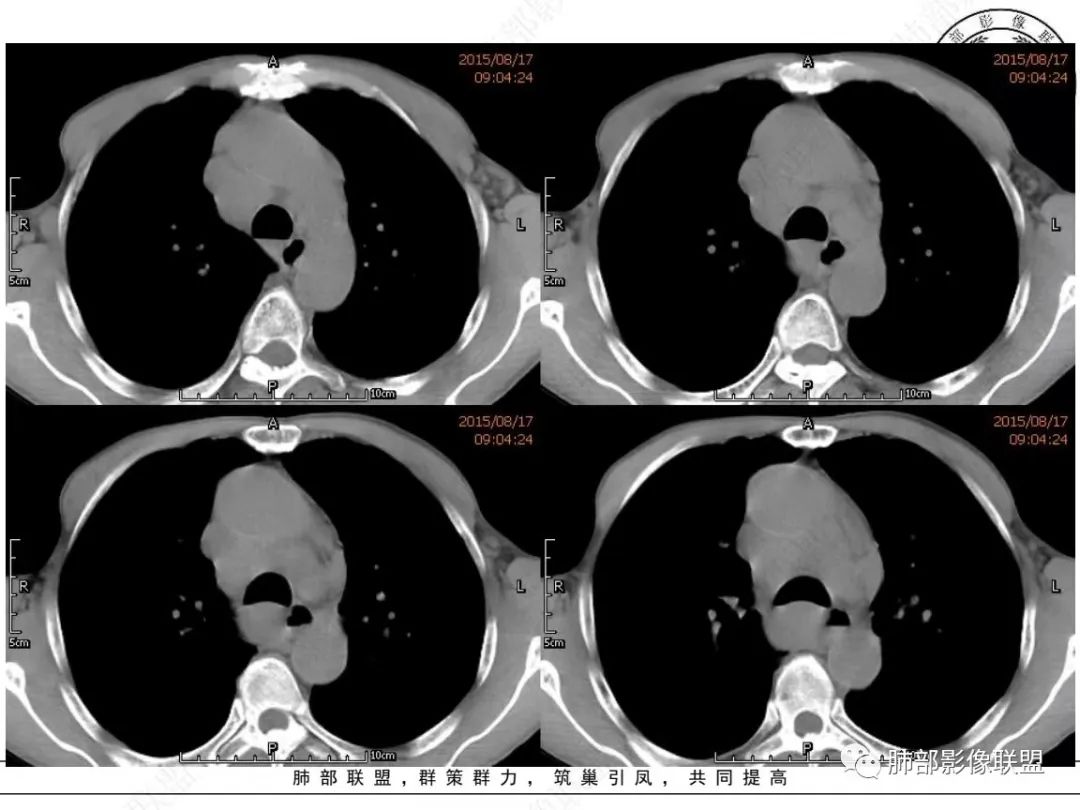

采莲:老年男性,有吸烟史,双颈部肿块,双肺纵隔淋巴结多发淋巴结肿大并融合成块,气管及右肺下叶支气管受压狭窄,考虑恶性,淋巴瘤可能,鉴别小细胞肺癌。

崔少钢:老年男性,有吸烟史,右肺下叶背段示小结节,纵隔、腋窝及右肺门淋巴结节肿大,气管受压狭窄,后纵隔软组织内示血管走行,考虑小细胞>淋巴瘤。

我只是邓较瘦:晨读老年男性,长期吸烟。右肺门、纵隔多发肿大淋巴结、融合成团块,中间支气管、右肺下叶支气管受压变窄,增强扫描强化程度较轻,血管包埋。另两侧腋窝亦见多发肿大淋巴结。常规恶性没问题,小细胞?淋巴瘤?但是於老师的病例总感觉没那么简单。

谢加平:纵隔内中后纵隔及右肺门淋巴结肿大,形成大肿块,整体密度均匀,并轻度强化,见“血管飘浮”征,包绕气管分叉及右主支气管及中间段支气管明显受压狭窄,并包埋右肺门血管束,无侵蚀破坏,右肺动脉后壁见压迹影,右肺下叶背段有阻塞性炎症,首选淋巴瘤,支气管超声内镜活检,明确诊断!

老年男性,颈部淋巴结而来,双侧对称,长期吸烟,双侧腋窝淋巴结肿大

,纵隔淋巴结肿大,特别是后纵隔,食道推移包绕,右肺门区支气管被包绕、受压狭窄。恶性应该没问题,问题是如何鉴别小细胞与淋巴瘤?

1、颈部、腋窝双侧淋巴结对称

2、右肺门区淋巴结肿大,但是没有沿支气管朝外延伸

3、食道没有梗阻

4、血管漂浮,走形自然

支持淋巴瘤